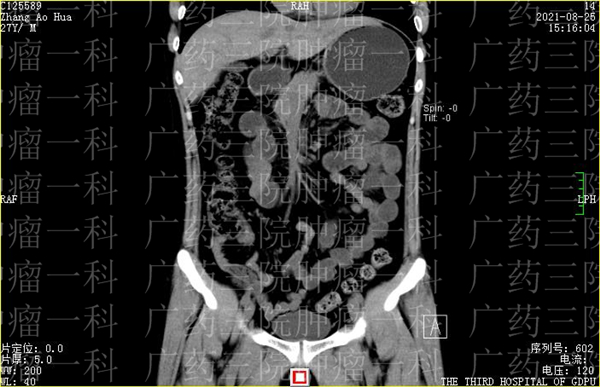

结合张先生过往的检查报告,医生认为,乙状结肠吻合口管壁较前增厚、代谢活跃,考虑肿瘤复发可能性大,多处出现代谢活跃结节、肿块,较前明显增大增多、代谢活跃,考虑种植转移或淋巴结转移,腹膜反折病灶局部侵犯邻近乙状结肠肠壁、右侧精囊腺及右侧盆壁腹膜,回盲部肠系膜区淋巴结多考虑反应性增生,右肺下叶后基底段的结节也不除外转移可能。

综上诊断,医生给出了诊断意见:1、乙状结肠癌术后化疗后复发,累及前列腺、 右侧精囊腺及乙状结肠:直肠系膜内稍大淋巴结。2、回盲部肠系膜间腺增大淋巴结,考虑反应性增生可能大。3双肺散在微小结节,较前相仿,暂考虑增殖灶可能,右肺中叶内侧段及左肺上叶下舌段炎性纤维灶。4、慢性胆囊炎;脾内多发钙化灶。5、右侧骼骨高密度影同前,考虑骨岛可能。

2021年8月26日,刘教授为张先生进行了微创消融手术治疗结肠癌。在DSA引导下,刘教授找到了肿瘤的供血血管,为张先生进行了肠系膜上动脉造影+灌注术、肠系膜下动脉造影+灌注术,通过灌药精准杀灭肿瘤。